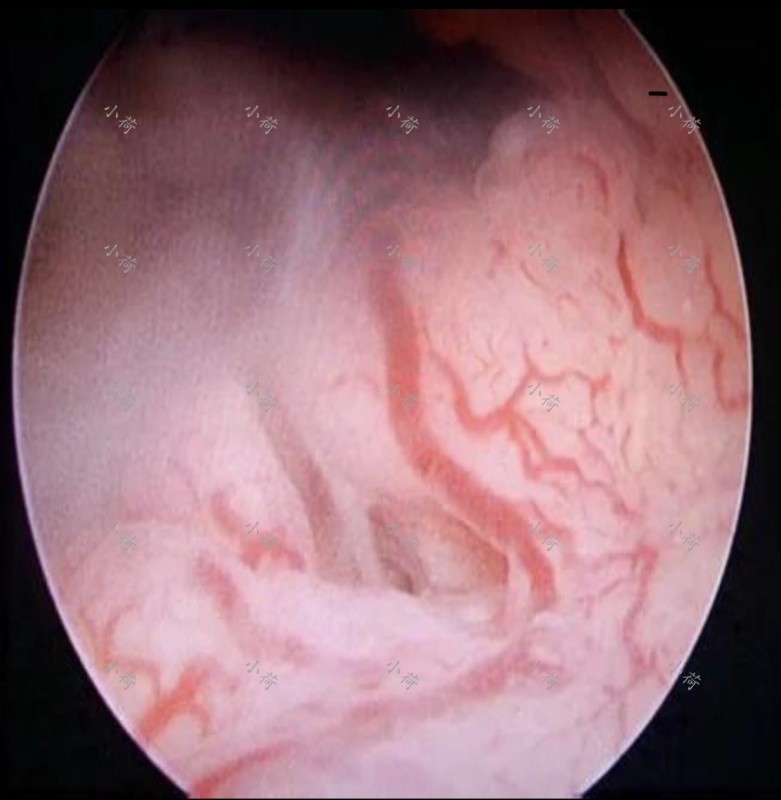

近两年老人膝关节退行性病变严重,并且时常犯糊涂,几乎丧失了自理能力。好在儿女们把老人家照顾的很周到。就诊前3个月,绝经多年的患者出现了少量阴道出血,并且血量有增多趋势。行妇科超声提示子宫萎缩欠佳、子宫内膜增厚,肿瘤标志物提示CA125轻度升高,外院行宫腔镜分段诊刮病理回报提示子宫内膜癌(图1),辗转多家医院后就诊于我院,诊断:子宫内膜癌I期?

图1 子宫内膜癌宫腔镜下所见